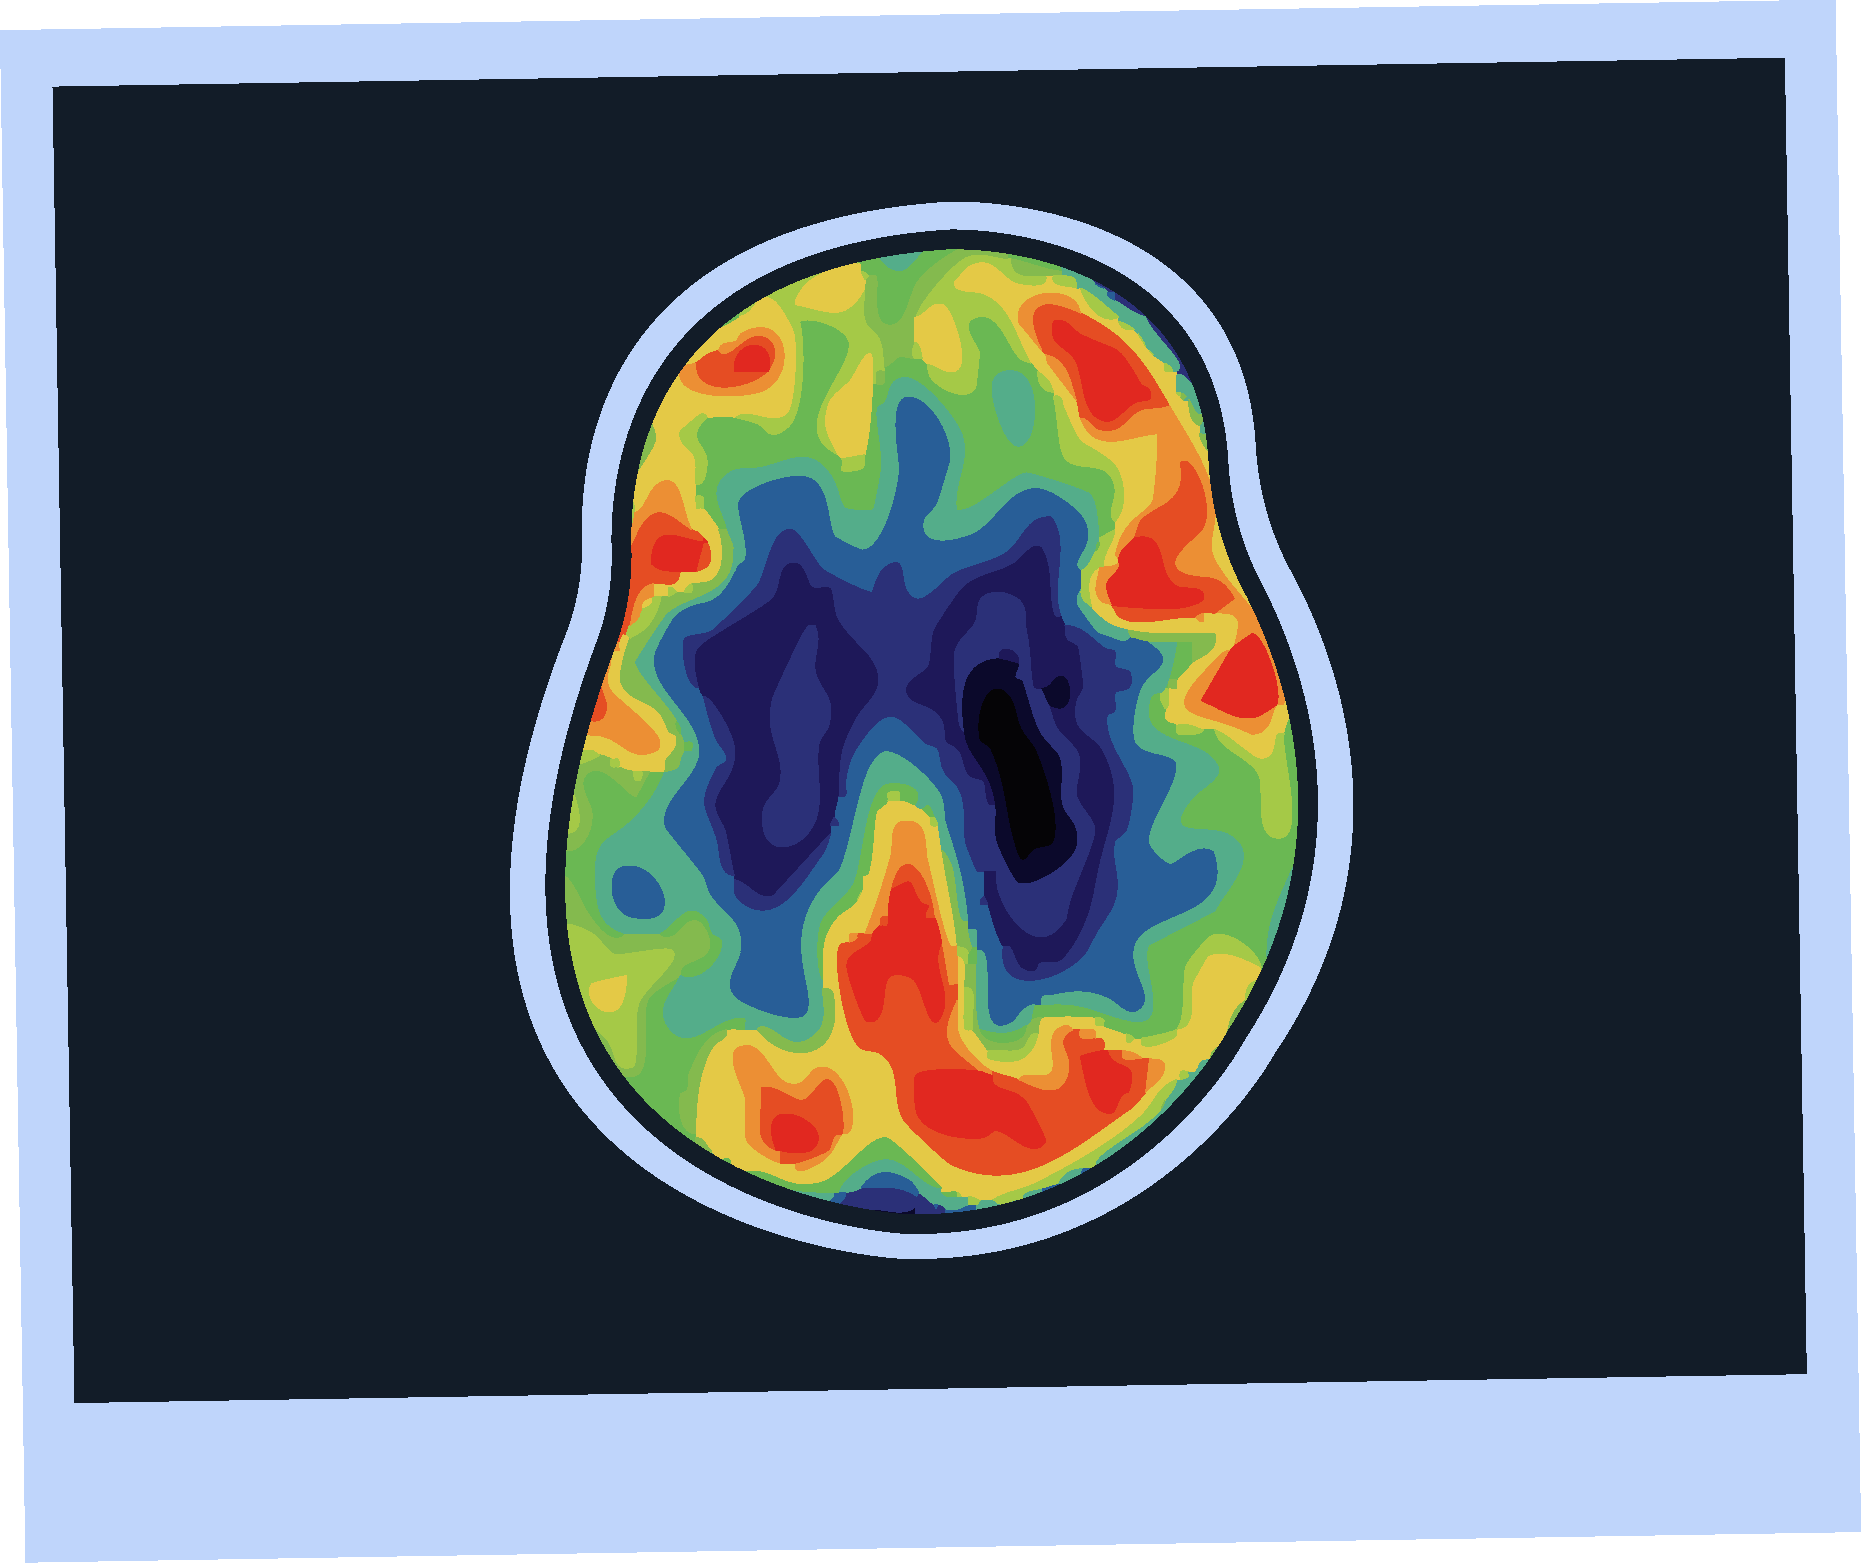

Amyloid PET Imaging

Strengths

Limitations

Sensitivity and specificity >90% for AD pathology.4

FDA approved and 2024 guideline endorsed.5

Minimally invasive.4

Validated versus post-mortem pathology.4

Limited availability.4

Involves radiation exposure.4

Does not assess other causes of cognitive impairment.4

Subject to inter-rater variability.4